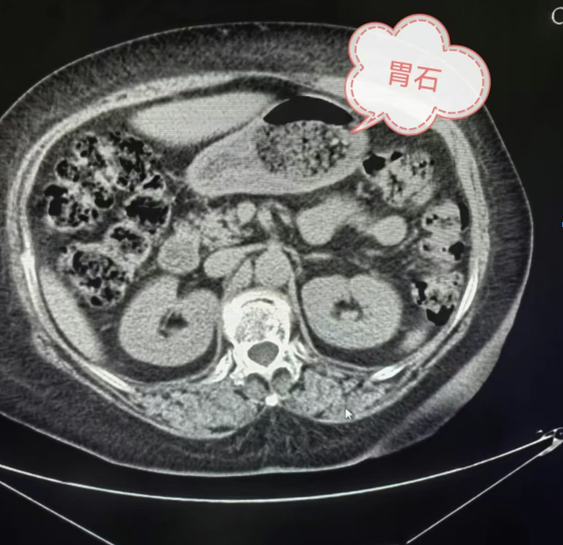

在胃結(jié)石的 CT 影像中,不同類型的結(jié)石有著獨(dú)特的“長相”。當(dāng)胃內(nèi)存在植物性結(jié)石時(shí),其影像表現(xiàn)通常為形狀不太規(guī)則的低密度影。仔細(xì)觀察,能看到內(nèi)部有散在分布的點(diǎn)、條狀稍高密度影,這是植物纖維的影像特征。若是混合性結(jié)石,CT影像則更為復(fù)雜,既有低密度的植物成分區(qū)域,又有因鈣化或其他礦物質(zhì)沉積形成的高密度區(qū)域,密度不均勻,邊界也相對模糊。例如:在一些長期存在的胃結(jié)石中,由于鈣鹽的不斷沉積,結(jié)石內(nèi)部會出現(xiàn)鈣化灶,在CT影像上表現(xiàn)為高密度影,與周圍低密度的植物成分形成鮮明對比。